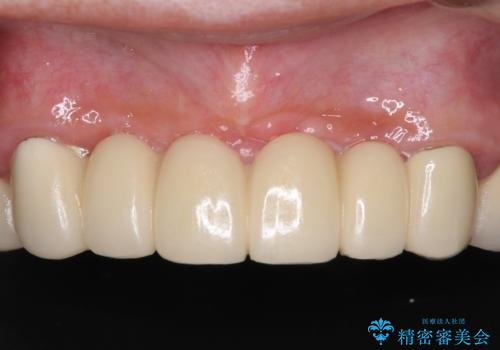

上下前歯の見え方を気にされており、歯だけをみると大変長くなりましたが、笑ったときの口元は自然な外見となり、患者様には大変満足していただきました。